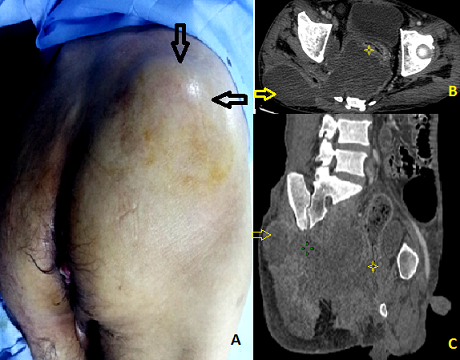

La perforation sous-péritonéale du cancer du rectum est rare. Sa découverte est souvent tardive par une infection périnéale sévère, nécessitant un diagnostic rapide et une prise en charge médico-chirurgicale urgente. Nous rapportons l'observation d'un patient présentant une perforation sous péritonéale d'un cancer rectal révélée par un abcès de la région fessière. Il s'agit d'un patient âgé de 44 ans, chez qui un adénocarcinome du bas rectum non métastatique a été récemment découvert, et qui consulte pour une tuméfaction douloureuse de la fesse droite apparu depuis une semaine et évaluant dans un contexte de fièvre et d'altération de l'état général. L'examen clinque note une tuméfaction rénitente chaude et sensible du quadrant supero-externe de la fesse droite d'environ 10 cm de diamètre (A). Le toucher rectal met en évidence un processus tumoral bourgeonnant circonférentiel situé à 2 cm de la marge anale. Le bilan biologique montre un syndrome infectieux franc: hyperleucocytose à 15000 /mm et C-réactive protéine à 144mg/dl. Le scanner abdomino-pelvien objective un énorme processus tumoral rectal nécrosé et perforé (astérisque) en sous péritonéal et compliqué d'une collection abcédée de l'excavation pelvienne; cet abcès fuse vers la région fessière à travers l'échancrure ischiatique (flèche) (B, C). Par ailleurs, il n'existe pas d'épanchement intra-péritonéal. Notre patient a été mis sous antibiothérapie à large spectre. Un drainage chirurgical de l'abcès à travers une incision en regard de la tuméfaction fessière a été effectué en urgence, ramenant 300 de pus francs et de débris tumoraux. Une sigmoidostomie de dérivation du flux fécal à été associée par voie élective. Quant au traitement du cancer rectal, il ne sera envisagé que secondairement, après avoir complètement contrôlé l'infection.